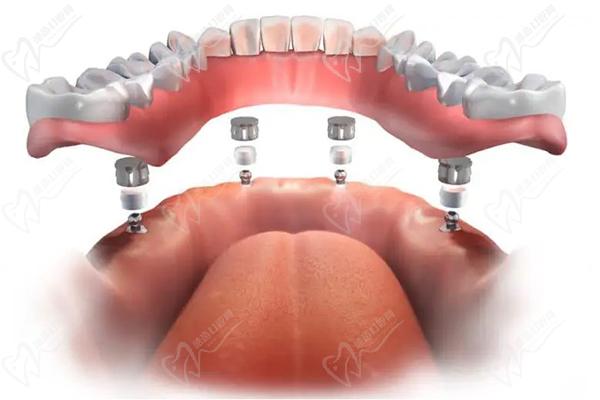

4、植入種植體佩戴牙冠:根據(jù)預(yù)先設(shè)計(jì)好的種植牙方案,在拔牙后的創(chuàng)口內(nèi)植入選定的種植體,確保種植體與牙槽骨緊密結(jié)合,并佩戴臨時(shí)牙冠,實(shí)現(xiàn)當(dāng)天種牙、當(dāng)天用牙。

全口即拔即種即刻負(fù)重種植牙一般分為兩期,一期手術(shù)是在拔除牙齒后立即植入種植體,戴臨時(shí)牙冠,等待創(chuàng)口愈合;二期手術(shù)則是待創(chuàng)口愈合后,進(jìn)行固定牙冠佩戴。全口即拔即種即刻負(fù)重可以同時(shí)全口做,也可以先上頜后下頜。在每期手術(shù)之間,醫(yī)生會根據(jù)患者的具體情況進(jìn)行相應(yīng)的藥物治療和護(hù)理指導(dǎo)。